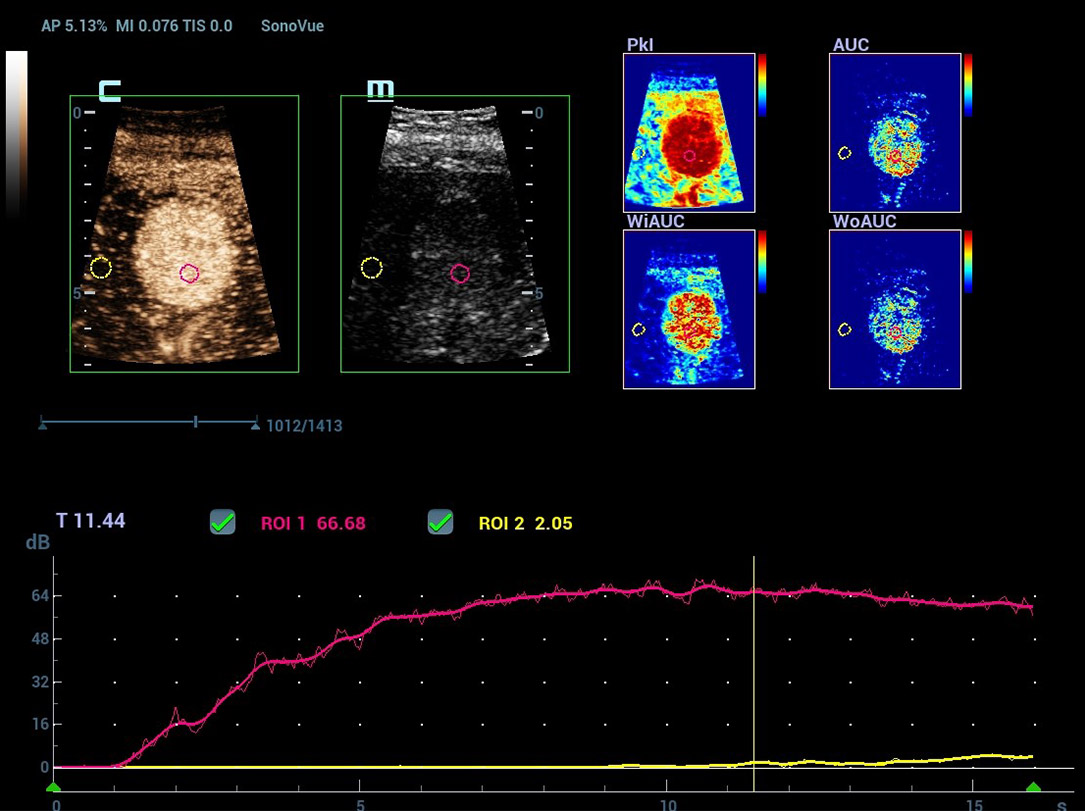

Nieuwe CEUS QA

Geavanceerde CEUS-kwantificatietools

Nieuwe CEUS-kwantificatieanalyse

Nieuwe CEUS QA Borst kwaadaardig

De tijd-intensiteitscurve maakt kwantitatieve analyse van CEUS-beeldvorming mogelijk. De nieuwe CEUS QA biedt tools voor geavanceerde kwantitatieve analyse die ondersteuning bieden bij tumorbeoordelingen en klinisch onderzoek.